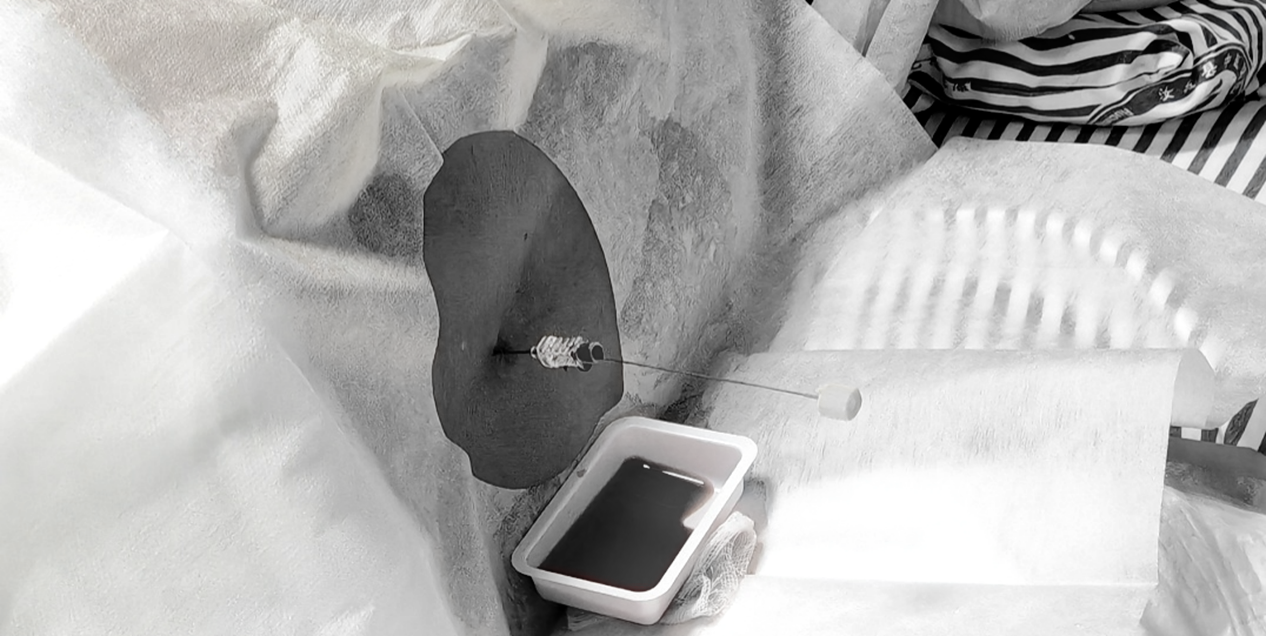

介入手术中

面对如此艰难的挑战,参与医学的团队以精湛的技术和无畏的勇气,利用支架协助弹簧圈栓塞技术,成功将特殊堵塞材料精确植入动脉瘤腔,完全阻挡血流冲击。

脑脊液更换